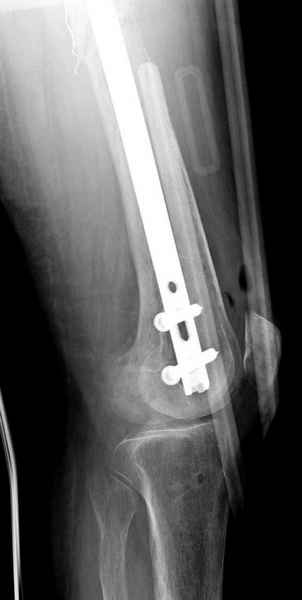

С минимальным рассверливанием и ретроградным методом провели остеосинтез бедра 12 мм гвоздем. (17-20)

Кровопотеря во время операции меньше 100 мл.

Больная выписана, взятый во время рассверливания материал изучается.